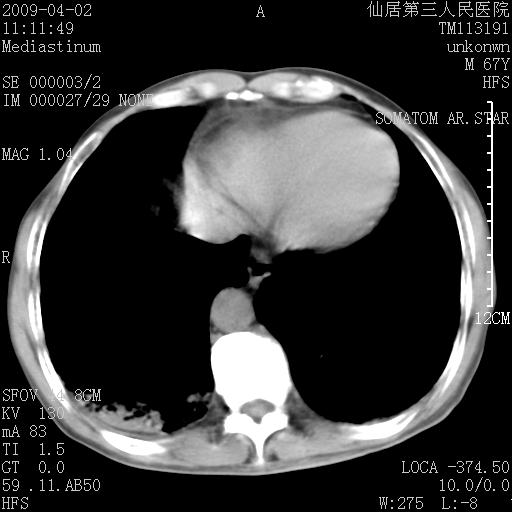

患者老年男性,乏力畏寒来诊,摄胸片示右下肺感染性病变,抗炎两周后复查胸片,无好转有进展。

后做ct平扫表现如下:

考虑右肺炎症可能性大,不除外细支气管肺泡癌

是否还要考虑肺间质纤维化,建议hrct扫描。

病灶呈蜂窝征,纵隔多个淋巴结肿大;肺泡癌需考虑

我认为普通的感染应该可以除外,间质性肺炎可能性较大,但如何解释纵膈的淋巴结肿大呢